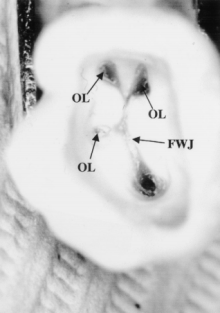

Law of orifice location 3: the orifices of the root canals are located at the terminus of the root developmental fusion lines.

orifices-of-canals-terminus-1

All the laws described previously are gathered in the following pictures: